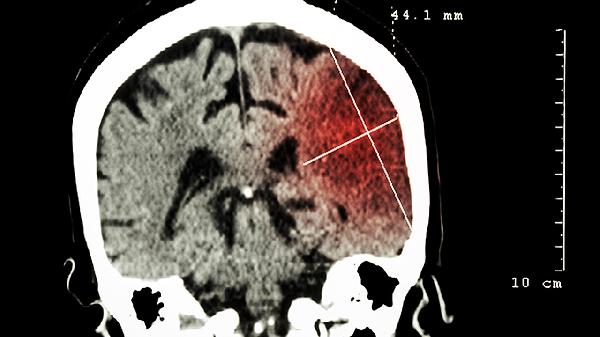

颅骨骨瘤通过头颅X线或CT可见界限清楚的骨性突起。脑瘤需依赖MRI增强扫描明确病变范围,必要时需进行病理活检。两者影像学特征具有显著差异。